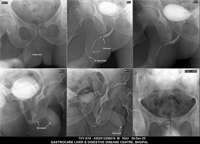

Section: URETHROGRAM Total: 95 images

BaM Enteroclysis Loopogram BaE Fistulogram Urethrogram HSG